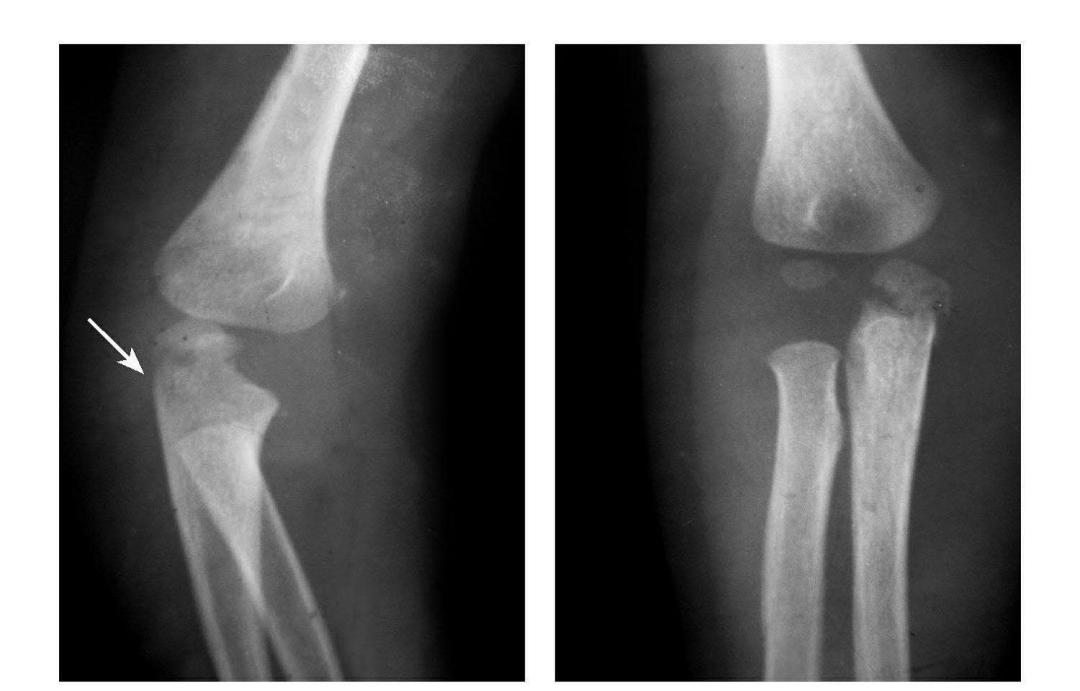

肱骨小头骨骺滑脱

例:肱骨小头骨骺向外移位并呈倾斜状。

肱骨下端双髁骨折

例1:肱骨内髁及外髁骨折,该两髁骨块均呈向内、外翻转移位。

例2:肱骨内上髁Ⅲ度骨折并外上髁撕脱骨折。

例3:肱骨内上髁Ⅳ度骨折并外上髁撕脱骨折。